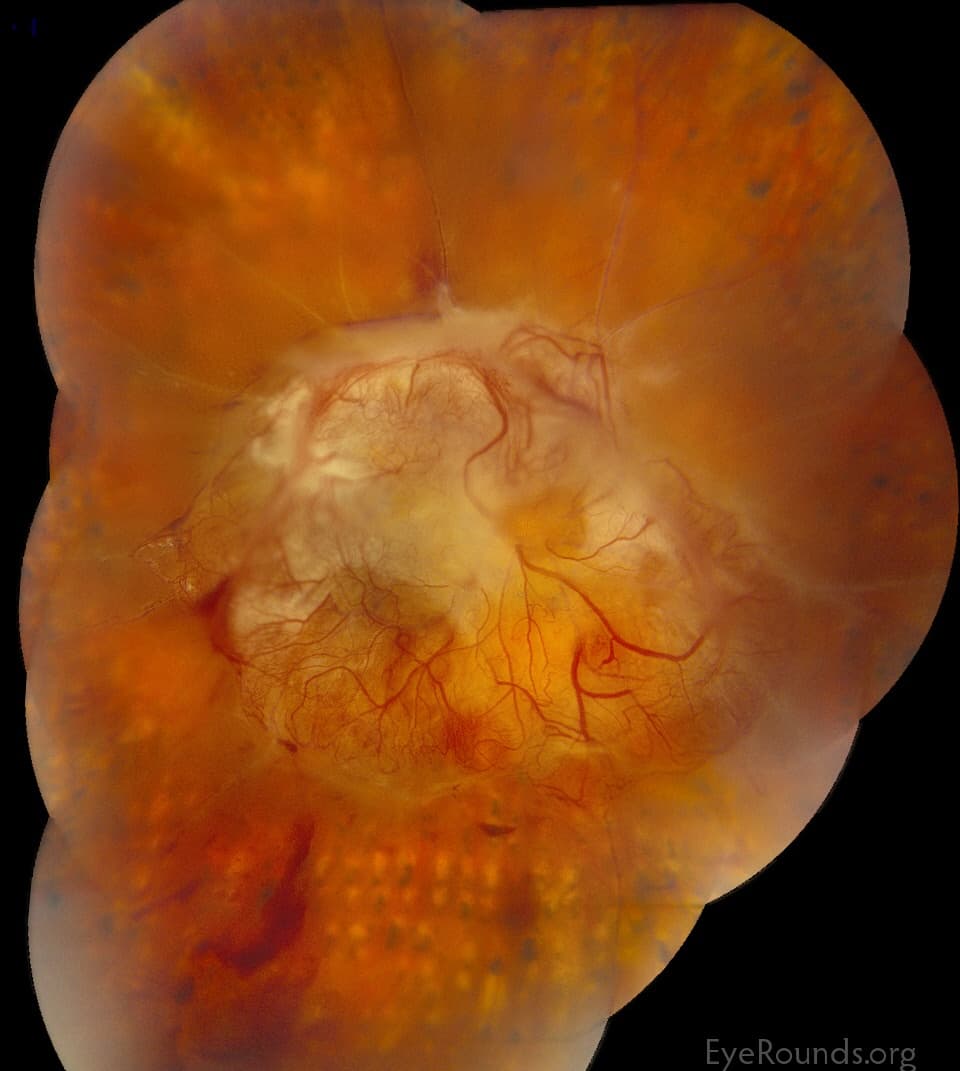

Diabetic retinopathy is a diabetes complication that affects the eyes. It's caused by damage to the blood vessels of the light-sensitive tissue at the back of the eye (retina).